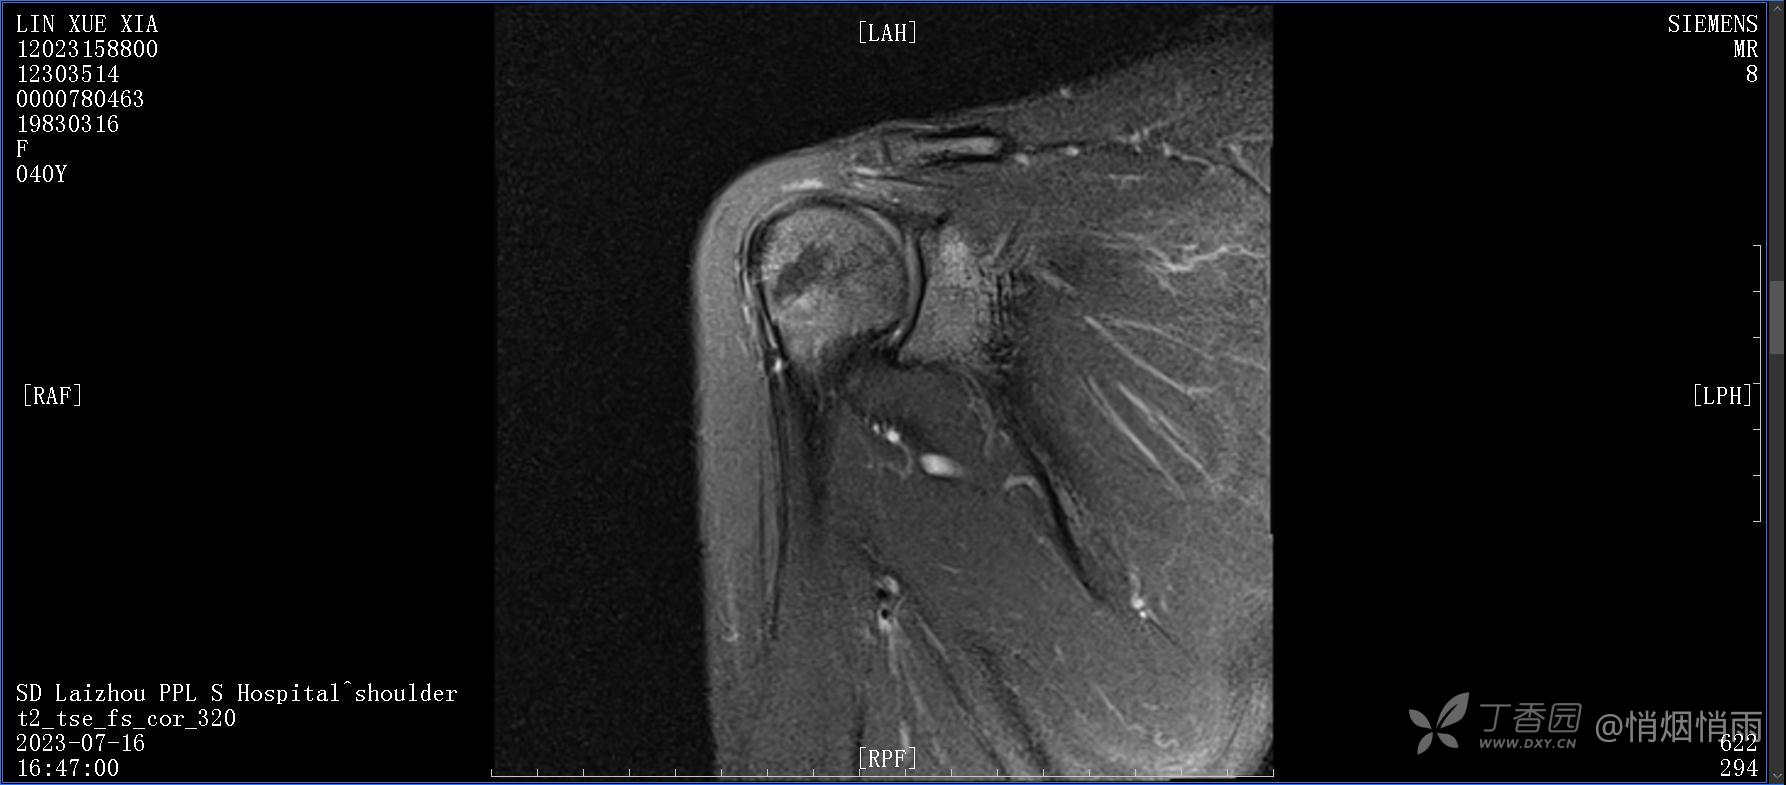

查体:右肩关节局部轻度肿胀,肩胛区压痛明显,痛处不固定,肩关节痛性活动受限,jobe test(+),lift -off test(+),中指、环指感觉较余指减退,余肢端感觉及血运情况可。

目前的诊断,暂时依据辅助检查诊为肩袖损伤,但是患者疼痛的性质和特点,却不是单纯的肩袖损伤所致。考虑过胸廓出口综合征,但是该疾病会出现肩胛区的疼痛吗?(由于考虑到费用的问题,没再进行下一步的检查)带状疱疹会有如此的症状吗?